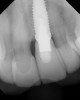

Fig 7. Implant transfer post in place.

Figure 7

The cantilever bridge and healing abutment were removed, and an implant impression post was screwed into the implant (Figure 7). After radiographic verification that the transfer post was completely seated, a closed-tray full-arch polyvinyl impression was taken. A facebow transfer jig, anterior bite registration, and opposing full-arch impression were also taken.